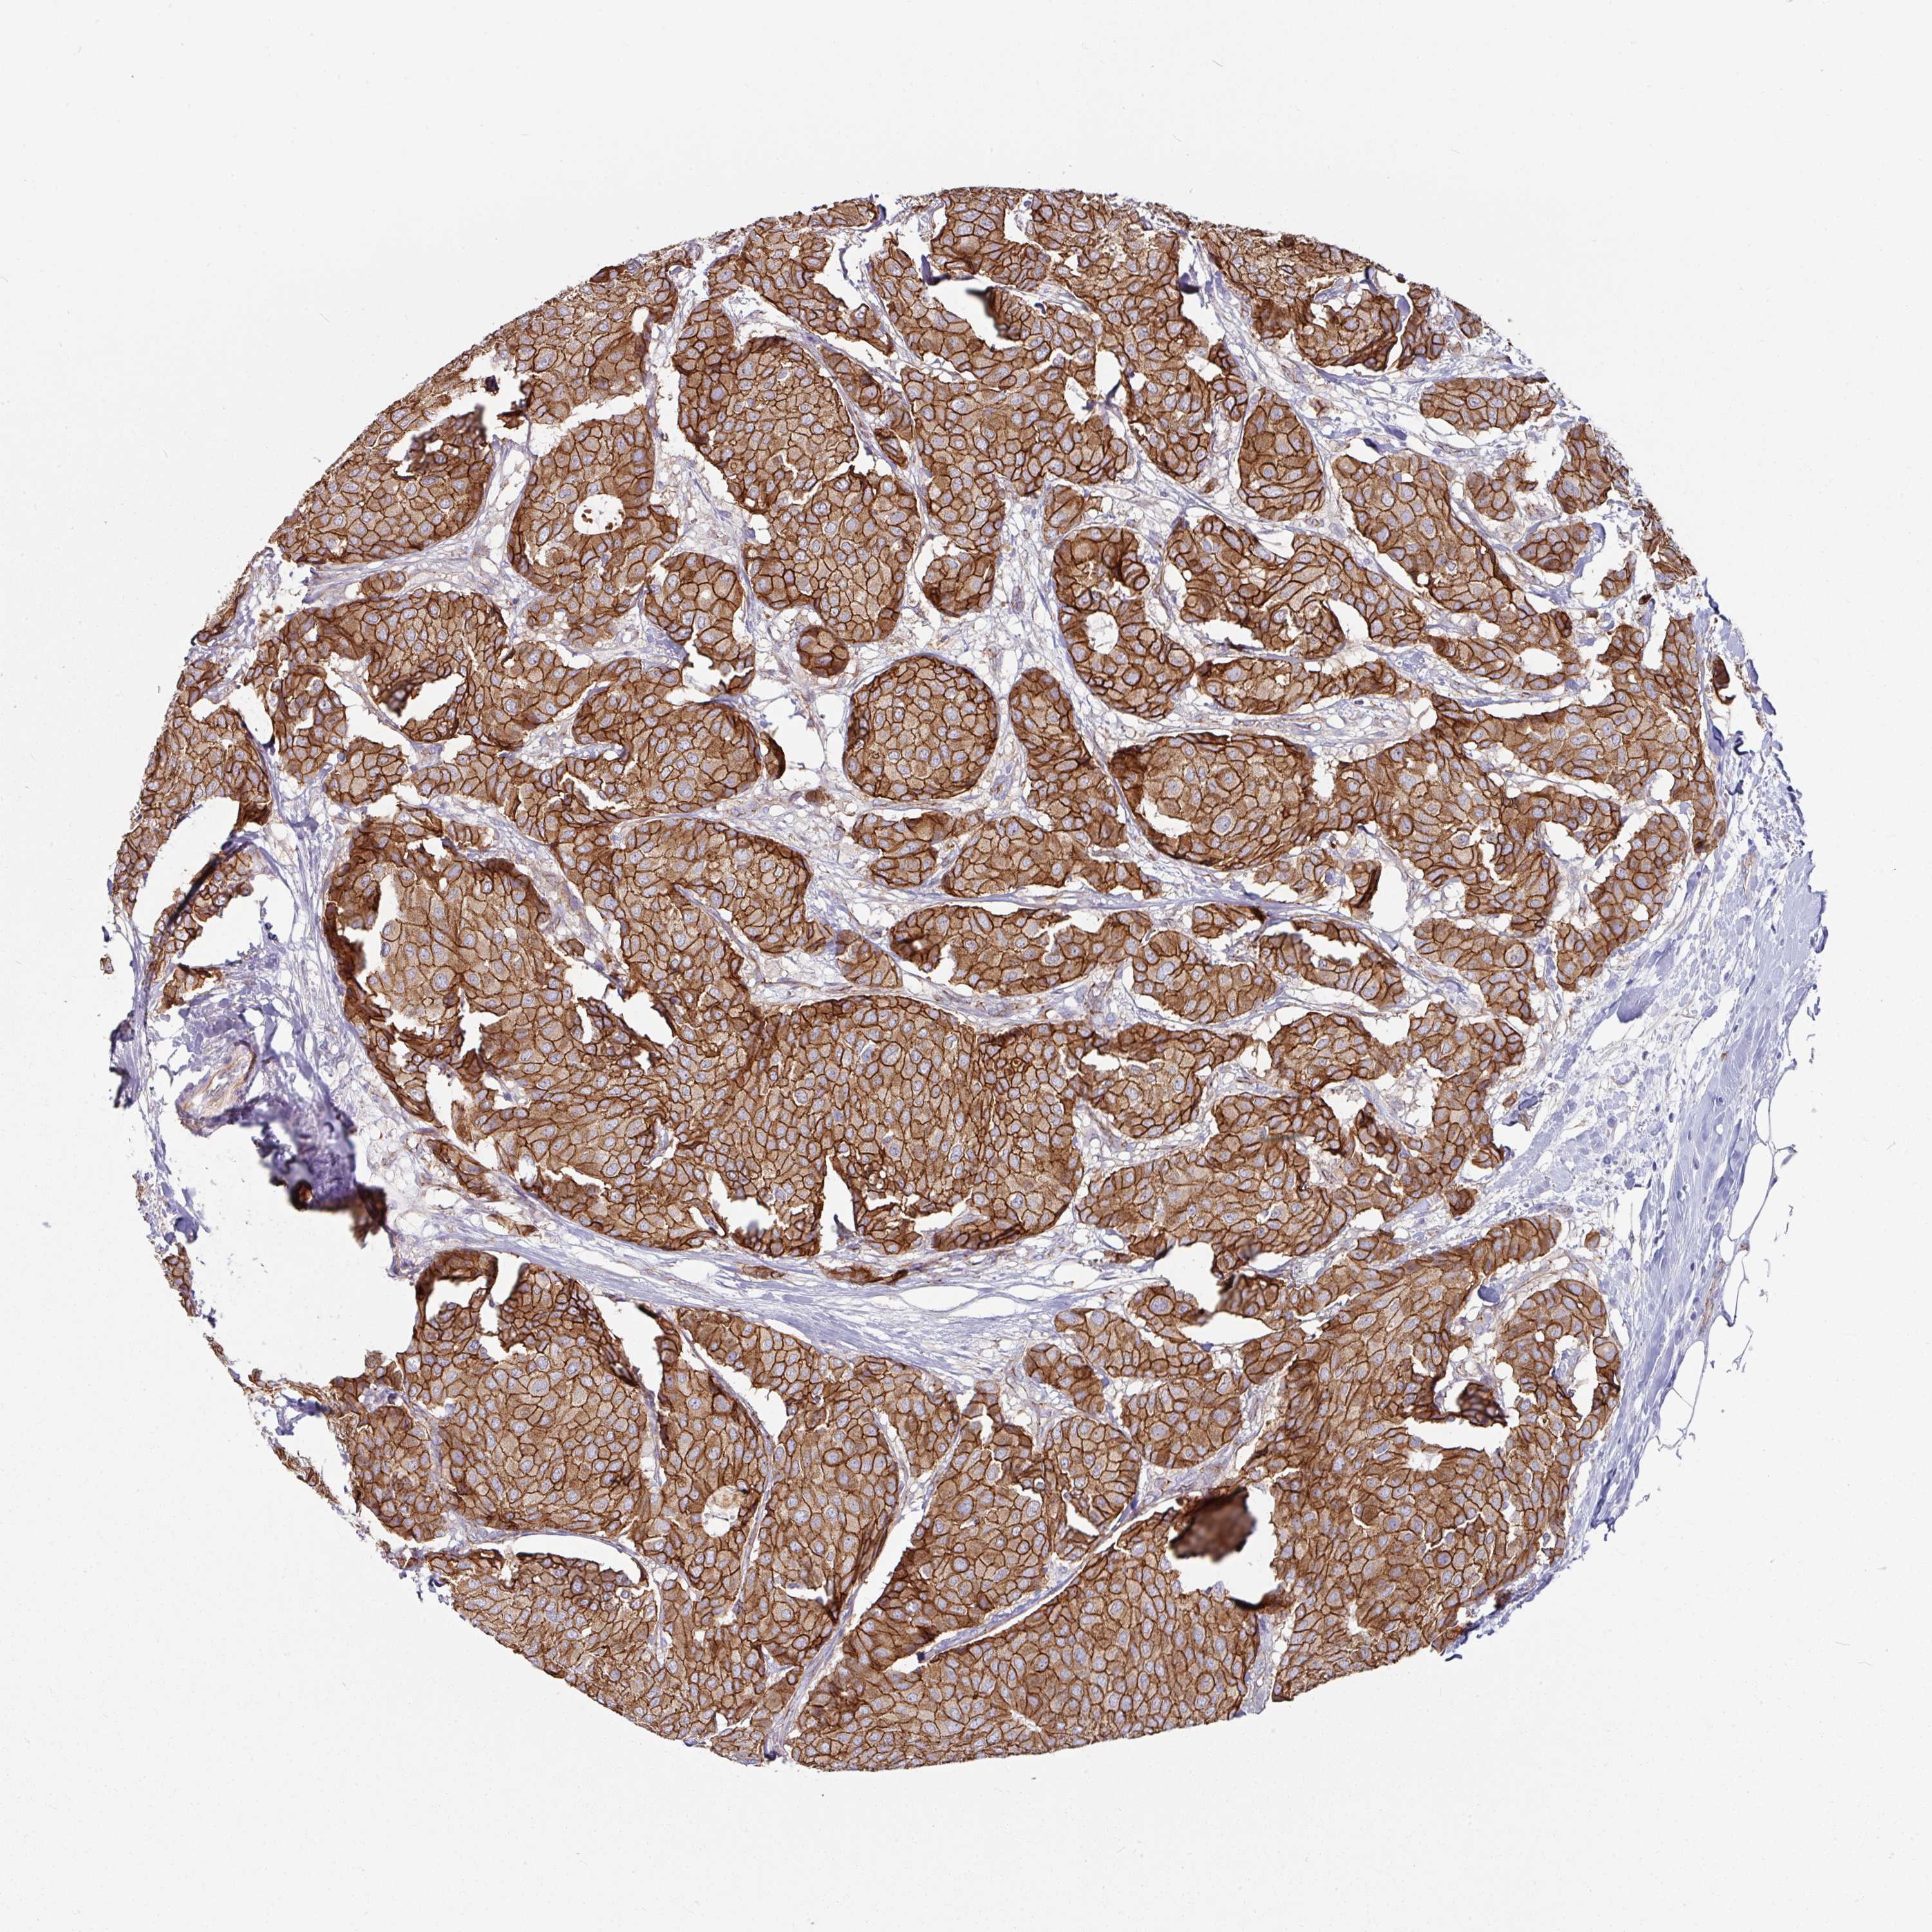

CANCER BREAST CANCER Show tissue menu

BRCA TCGA BRCA VALIDATION PROTEIN EXPRESSION